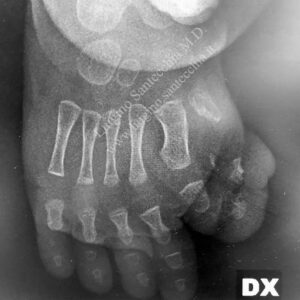

After